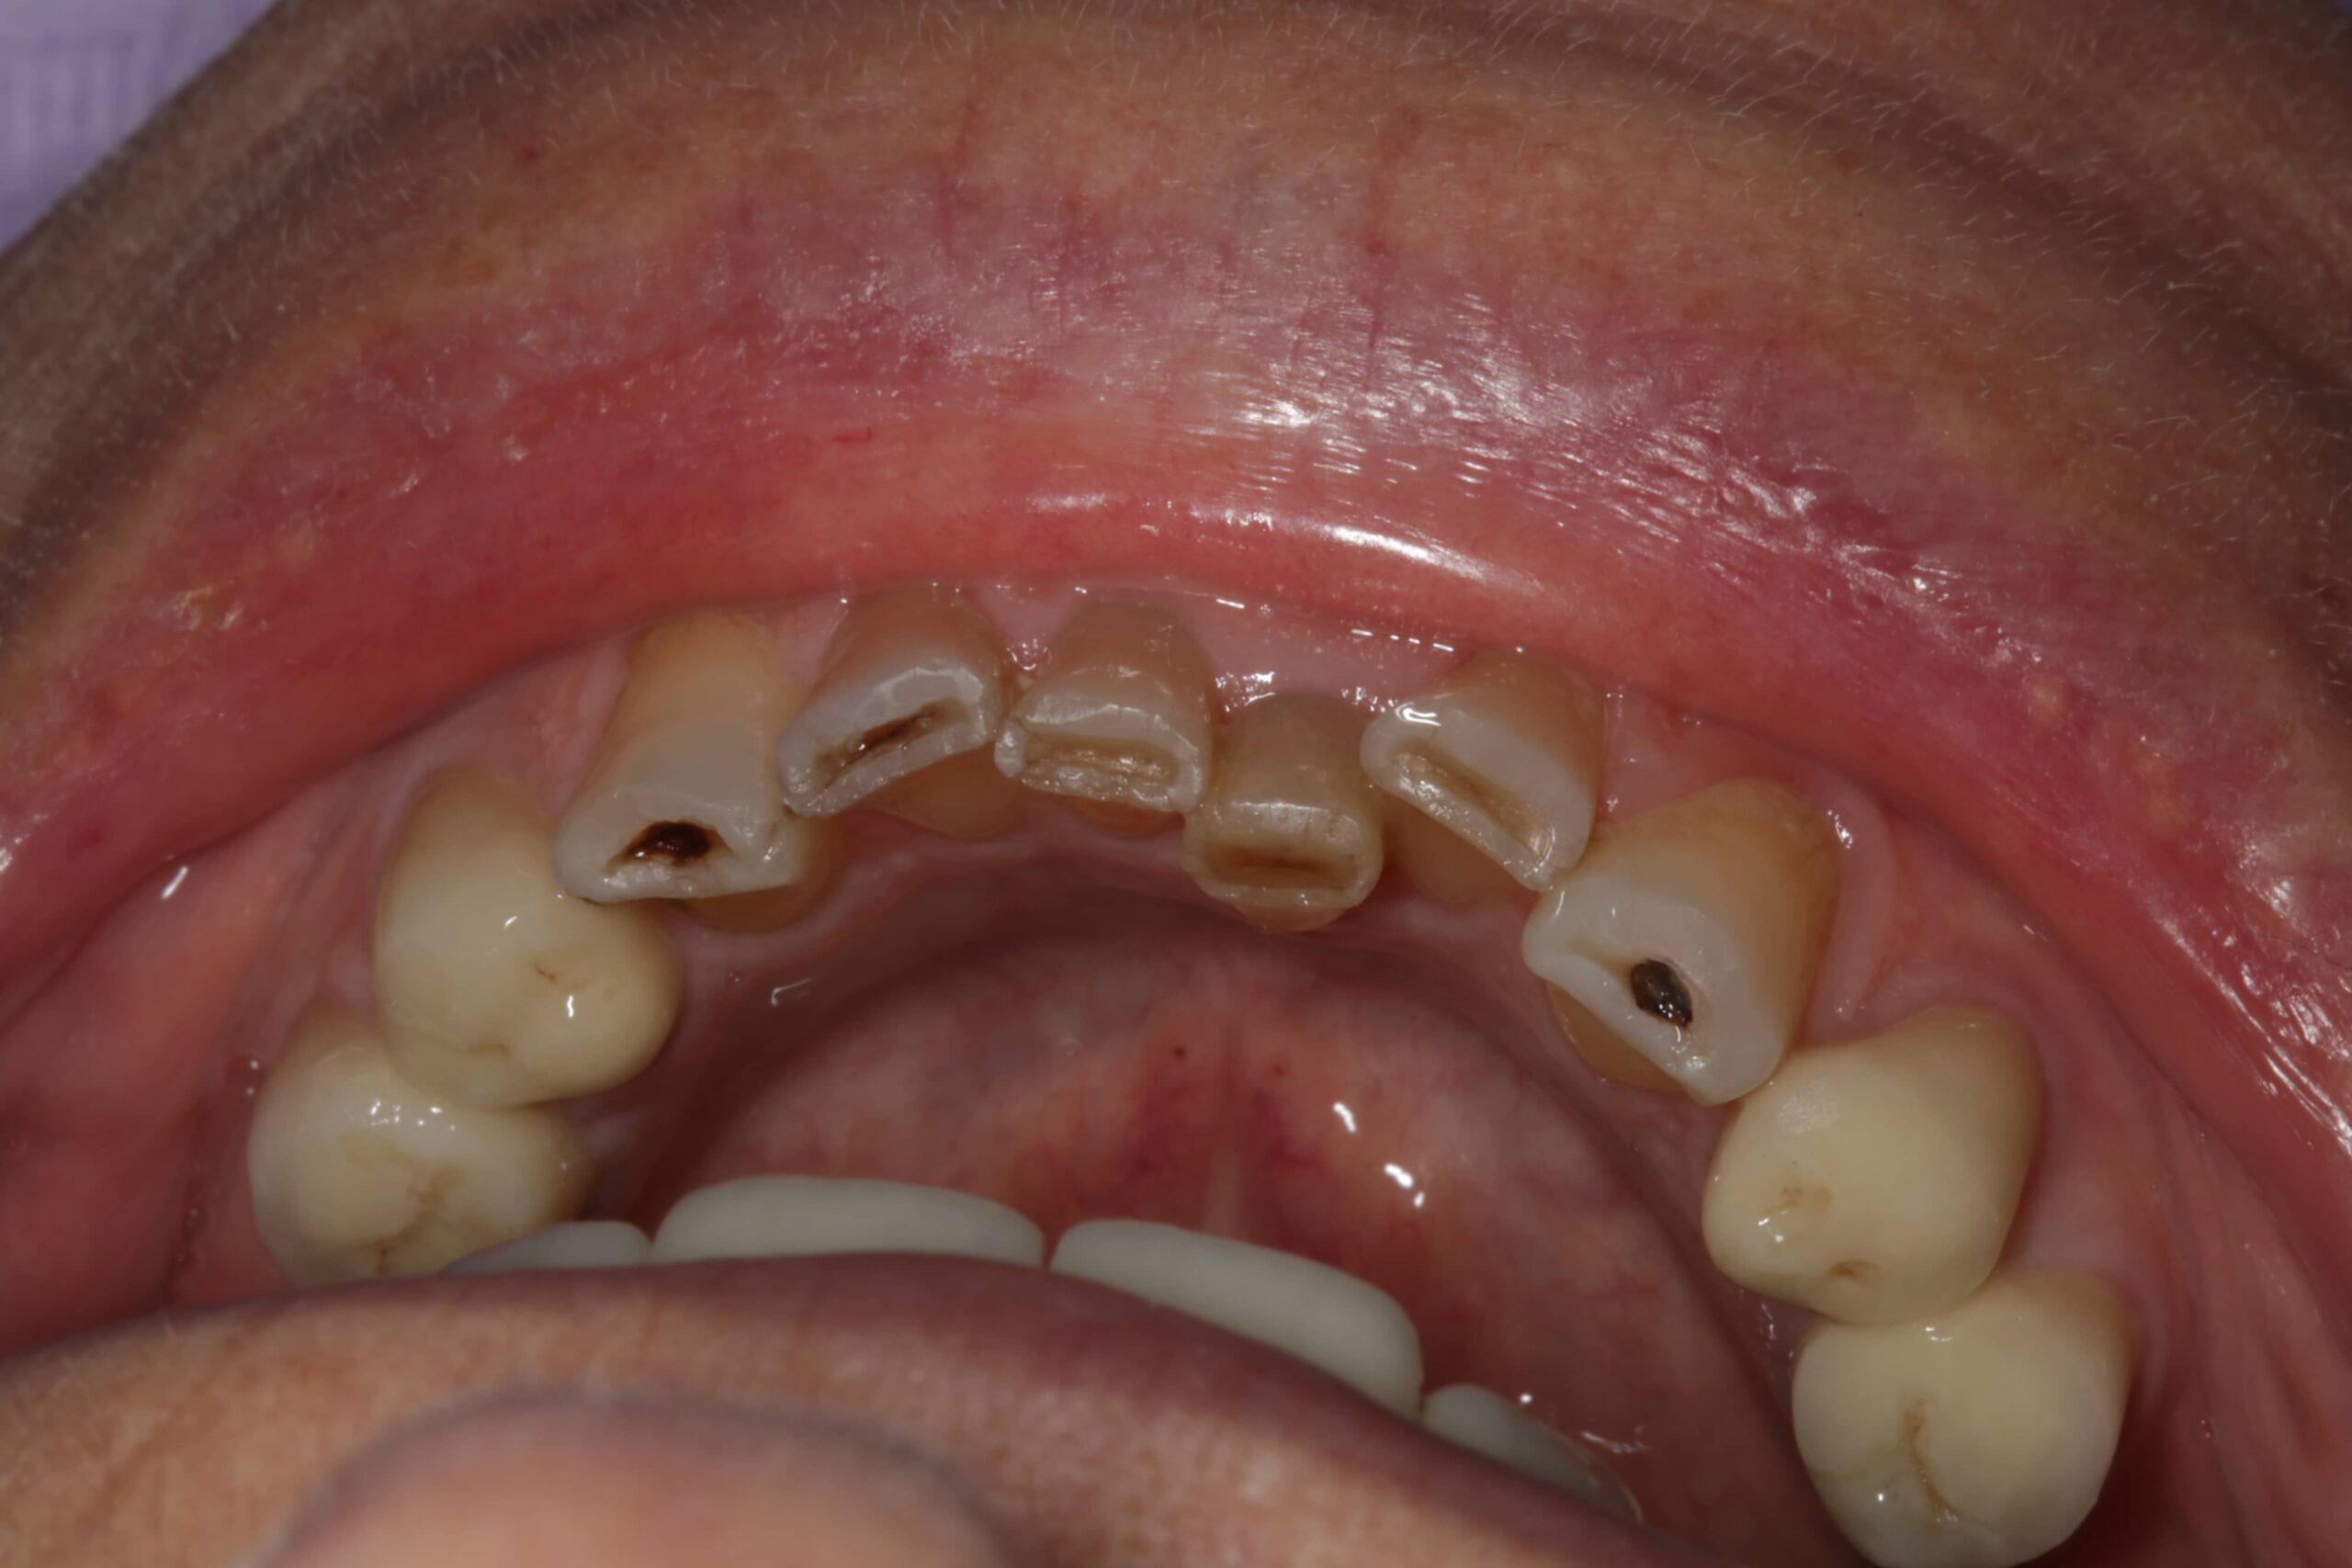

2. Fogászati eredetű fájdalmak

A fogak és az állkapocs közeli kapcsolatban állnak egymással, így számos fogászati probléma válthat ki állkapocsfájdalmat:

- Fogfájás: például gyökércsatorna-gyulladás vagy tályog

- Foghúzás utáni szövődmények: gyulladás, fertőzés, száraz fogmeder

- Bölcsességfog: különösen az előtörés során vagy a ferdén nőtt bölcsességfogak nyomása esetén alakulhat ki állkapocscsont fájdalom

- Nem megfelelően kialakított fogpótlások: rosszul illeszkedő koronák, hidak vagy kivehető pótlások hosszú távon megváltoztathatják a harapási viszonyokat, túlterhelhetik az állkapocsízületet, és funkcionális egyensúlyzavart idézhetnek elő. Ez gyakran vezet feszüléshez, rágás közbeni fájdalomhoz vagy ízületi kattogáshoz.